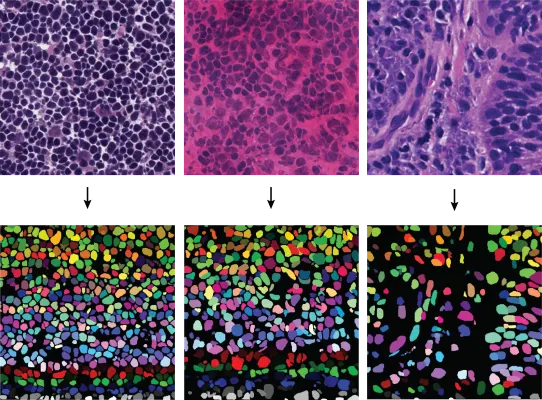

Deep Learning for Improved Nuclei Segmentation in Microscopic Images

Dr. Amirreza Mahbod presents how deep learning enhances nuclei segmentation and tackles challenges in histological image analysis.

How Deep Learning is Used for Cell Counting

Deep learning is transforming cell counting by enabling precise nuclei segmentation, even in dense tissue microenvironments. Learn how TissueGnostics applies deep neural networks (DNNs) to automate and improve accuracy in tissue cytometry workflows.

How Cell Counting Algorithms Work

Cell counting is central to biomedical research, but accuracy depends on advanced algorithms. This blog explores manual vs automated methods, and how TissueGnostics’ AI-driven cell counting algorithms enable reliable, high-throughput image-based analysis.